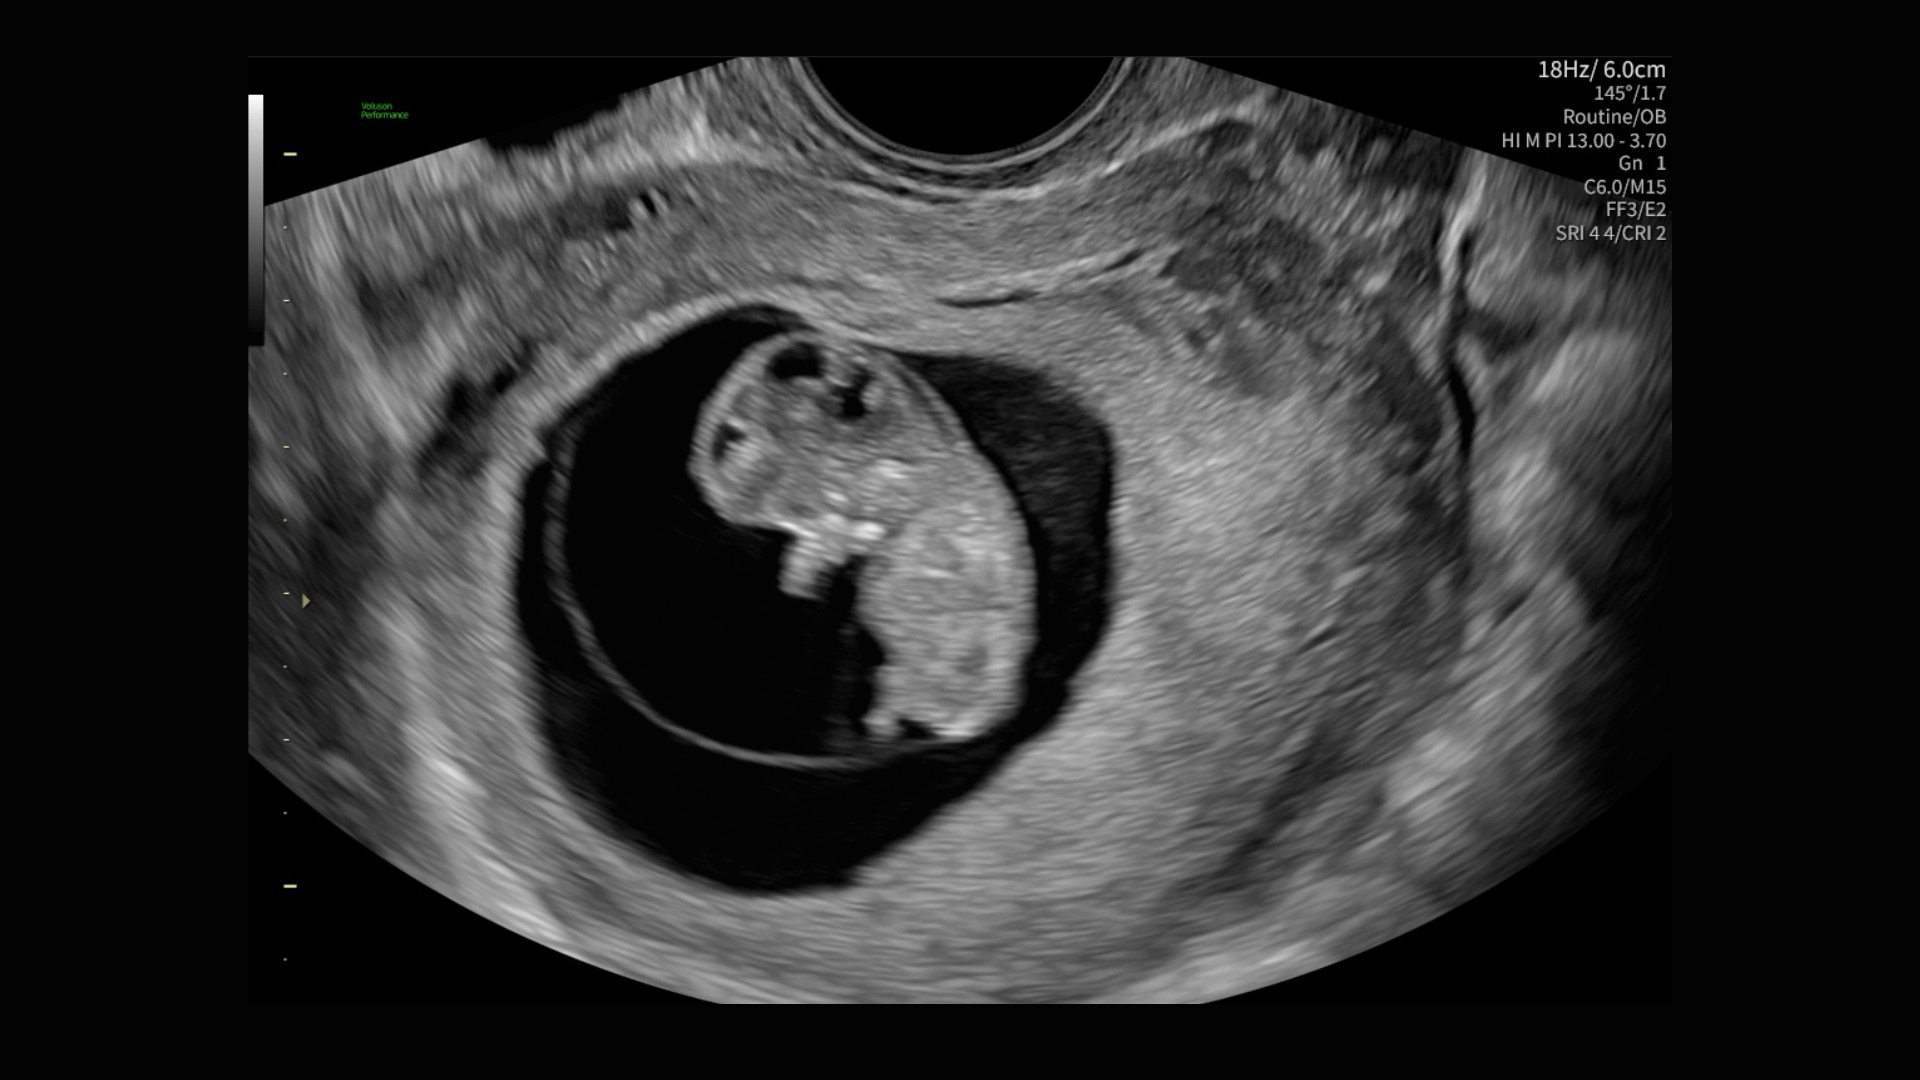

Image quality

Excellent images that are easy to acquire

Image quality is everything in ultrasound

The Voluson Performance 18 delivers high-resolution, detailed imaging with one-touch optimization for effortless scanning—helping you deliver quick, confident answers across a wide range of patient.